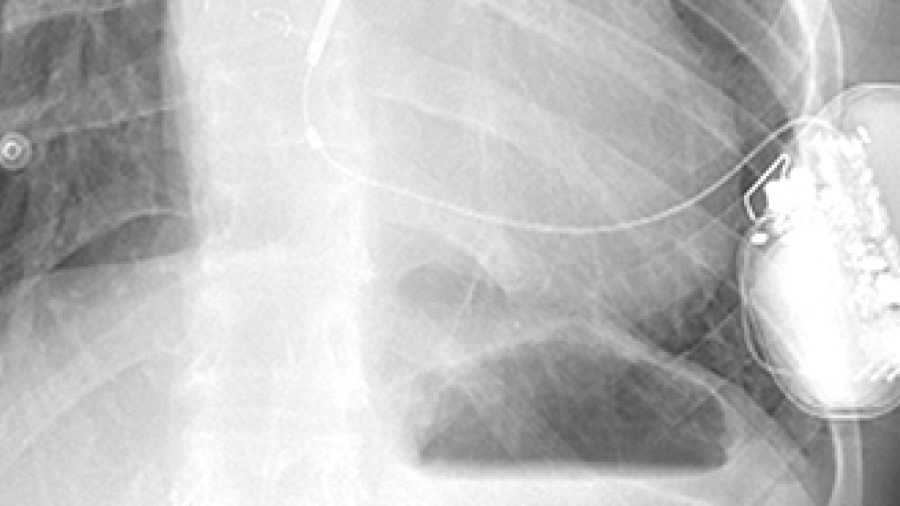

Réduire les radiations en imagerie cardiaque